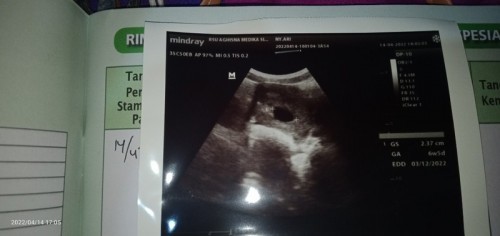

buun mo tanya usg 6w5d baru keliatan kantong janin. baiknya usg lagi kapan yaa? soalnya sewaktu usg, kalo sesuai HPHT harusnya 9w5d tapi di usg jadi segitu sampe sekarang kawatir banget. kawatir bun naudzubillah amit amit aku takut perkembangan berenti sampe 6w5d apa emang bener usia 6w5d masih belum keliatan janinnya. bunda yang pernah pengalaman atau tau info macem ini #pleasehelp #bantusharing aku butuh penenang + yang terbaik buat si utun😣😭